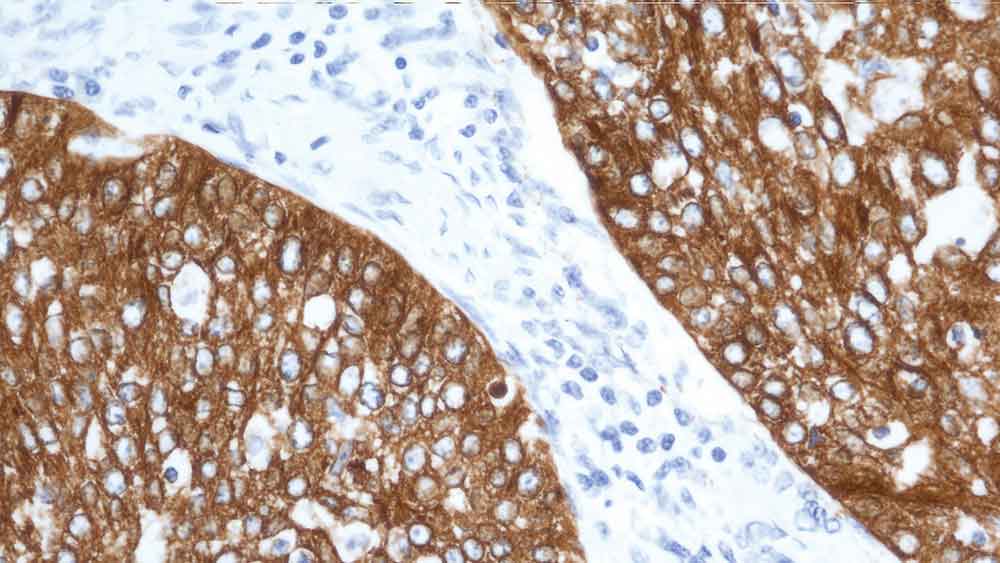

Human rectal adenocarcinoma: immunohistochemical staining for Cytokeratin 19. Note: cytoplasmic staining of malignant epithelial cells. Cytokeratin 19: clone b170

The smallest human cytokeratin filament protein (40 kD) has been identified as cytokeratin 19 and has been reported to be expressed in many epithelial cell types, including many ductal and glandular epithelia.

Clone B170 produces a complex heterogeneous staining pattern in non-keratinizing squamous epithelia and hair follicles, with strong staining of the basal layer observed.